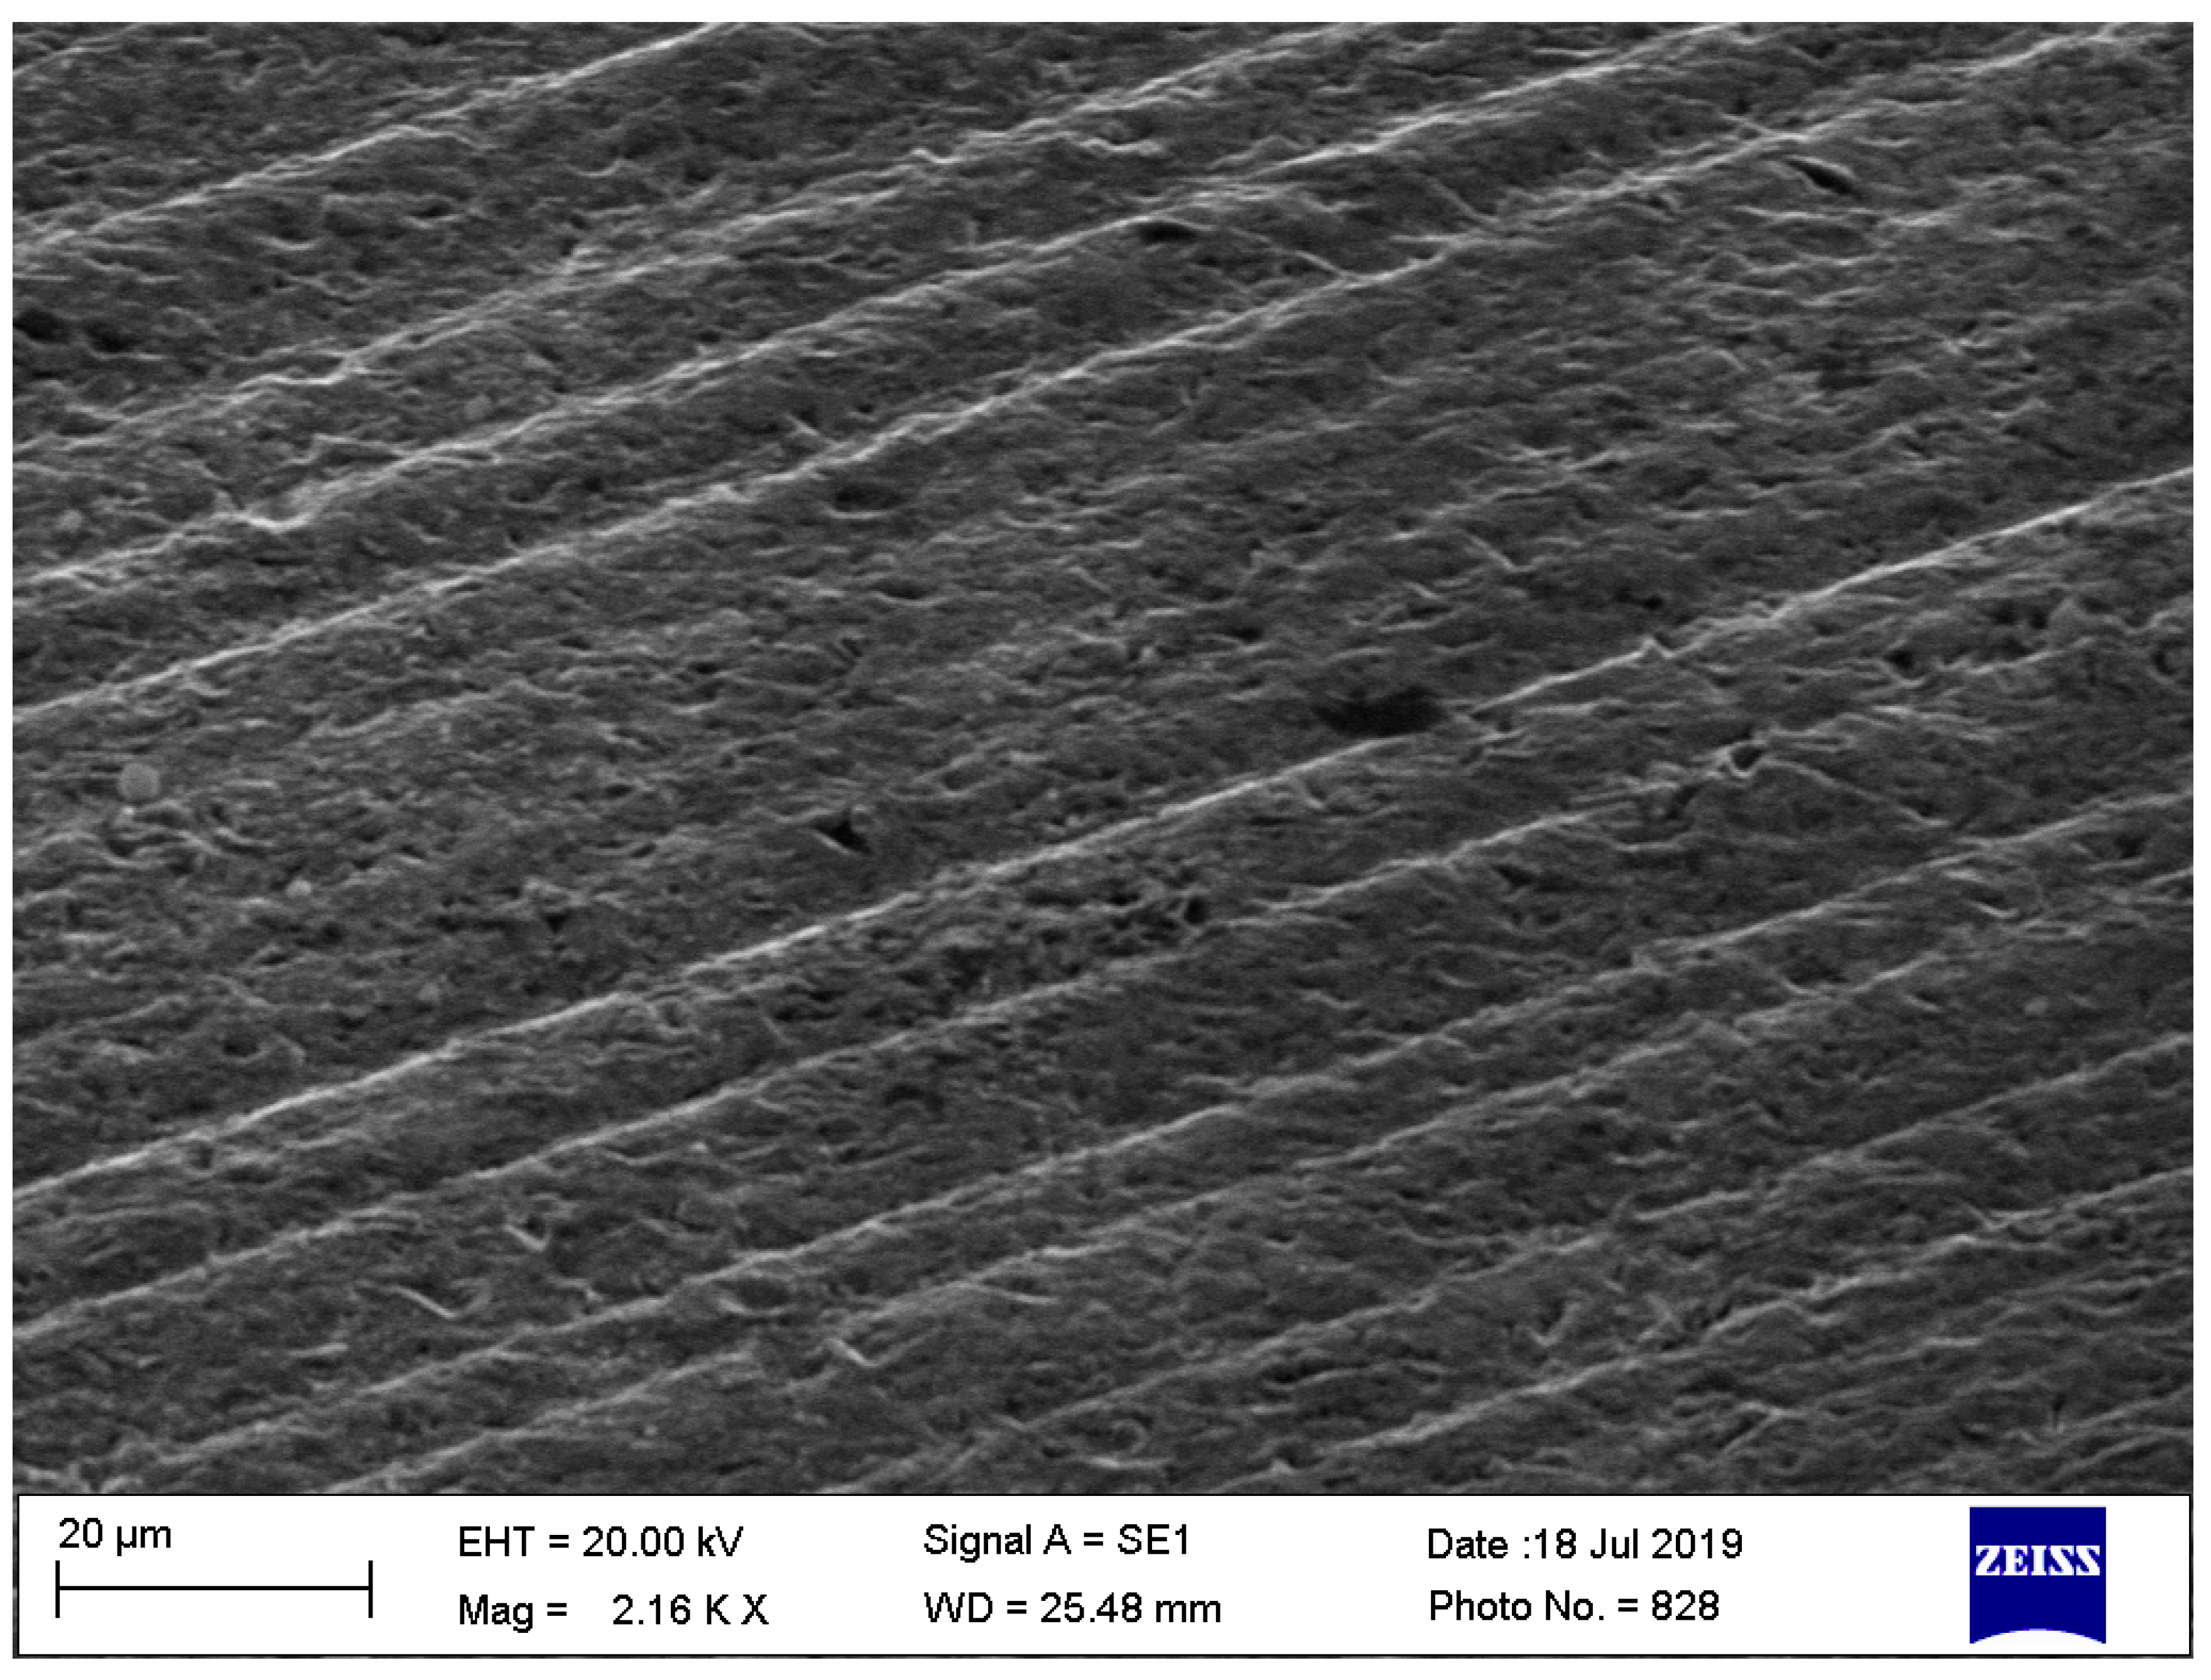

3.2. Scanning Electron Microscopy-EDS Analysis

3.2.1. Non-Sterilized Drill and Conical Tapper

3.2.2. Used and Sterilized Drill and Conical Tapper